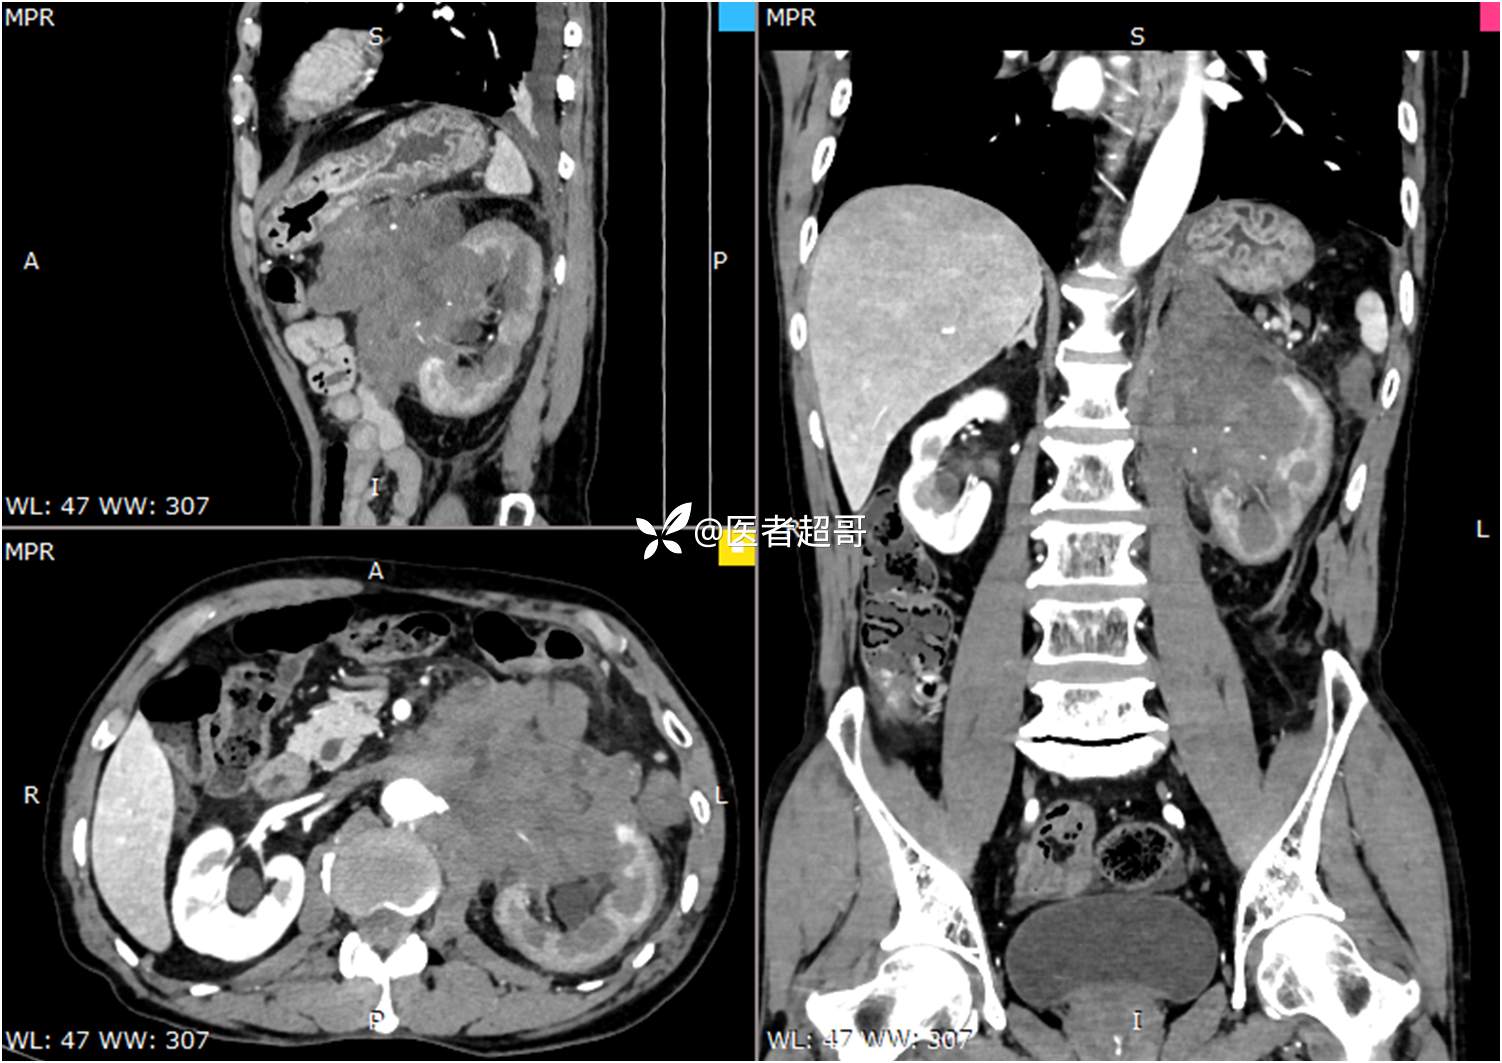

现病史:患者于1月前无明显原因及诱因出现左上腹部疼痛,为间断性疼痛,无恶心、呕吐,无寒战、高热,无腹胀、腹泻等伴随症状,在外未行特殊处理,患者于1周前自觉疼痛加重,为求诊治患者曾就诊于市东城医院,行全腹部强化CT提示:左肾上腺区肿块,符合恶性肿瘤侵犯左肾、胰腺及腹膜后大血管CT表现,行保守治疗,症状缓解,今患者为求进一步诊治,来我院就诊,行腹膜后占位穿刺活检病理提示:(腹膜后占位穿刺)小细胞背景内见细胞浆红染的神经节样细胞,建议到病理科加做免疫组化进一步明确诊断,遂以“腹膜后肿物”收入院,患者自发病以来,神志清,精神可,饮食、睡眠差,大小便正常,体重未见明显改变。